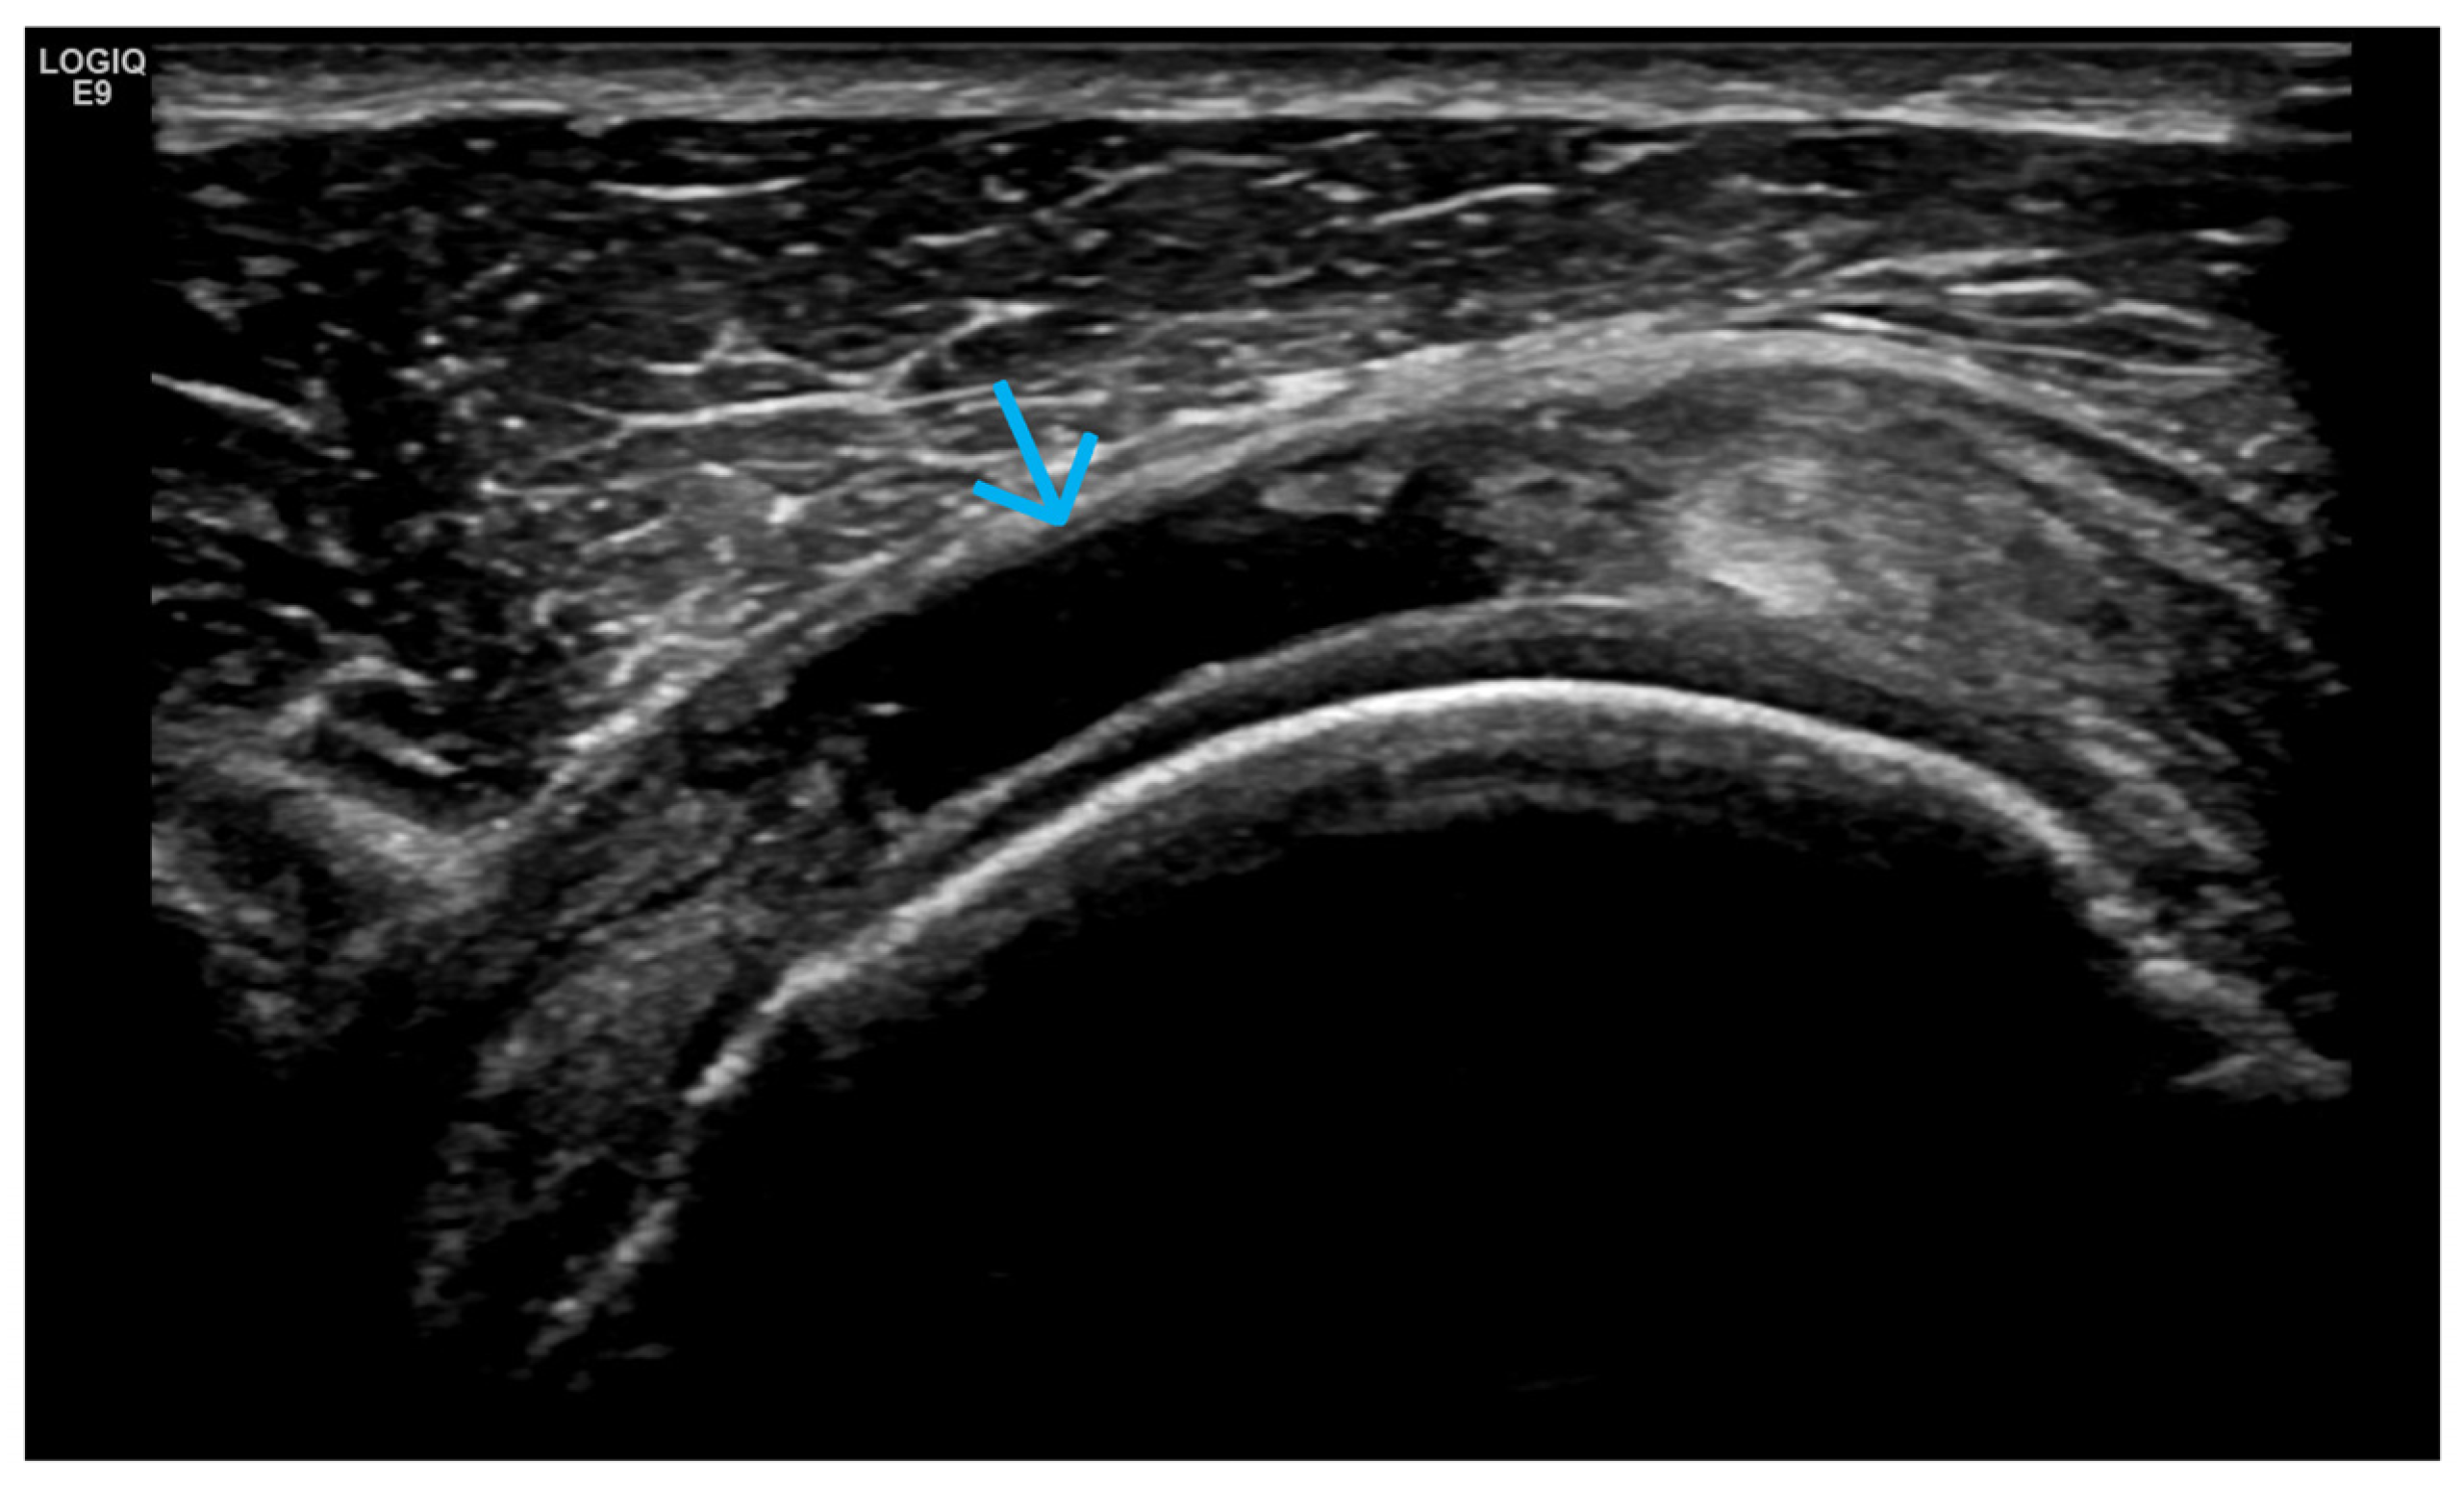

4. Examples of US Phenotypes